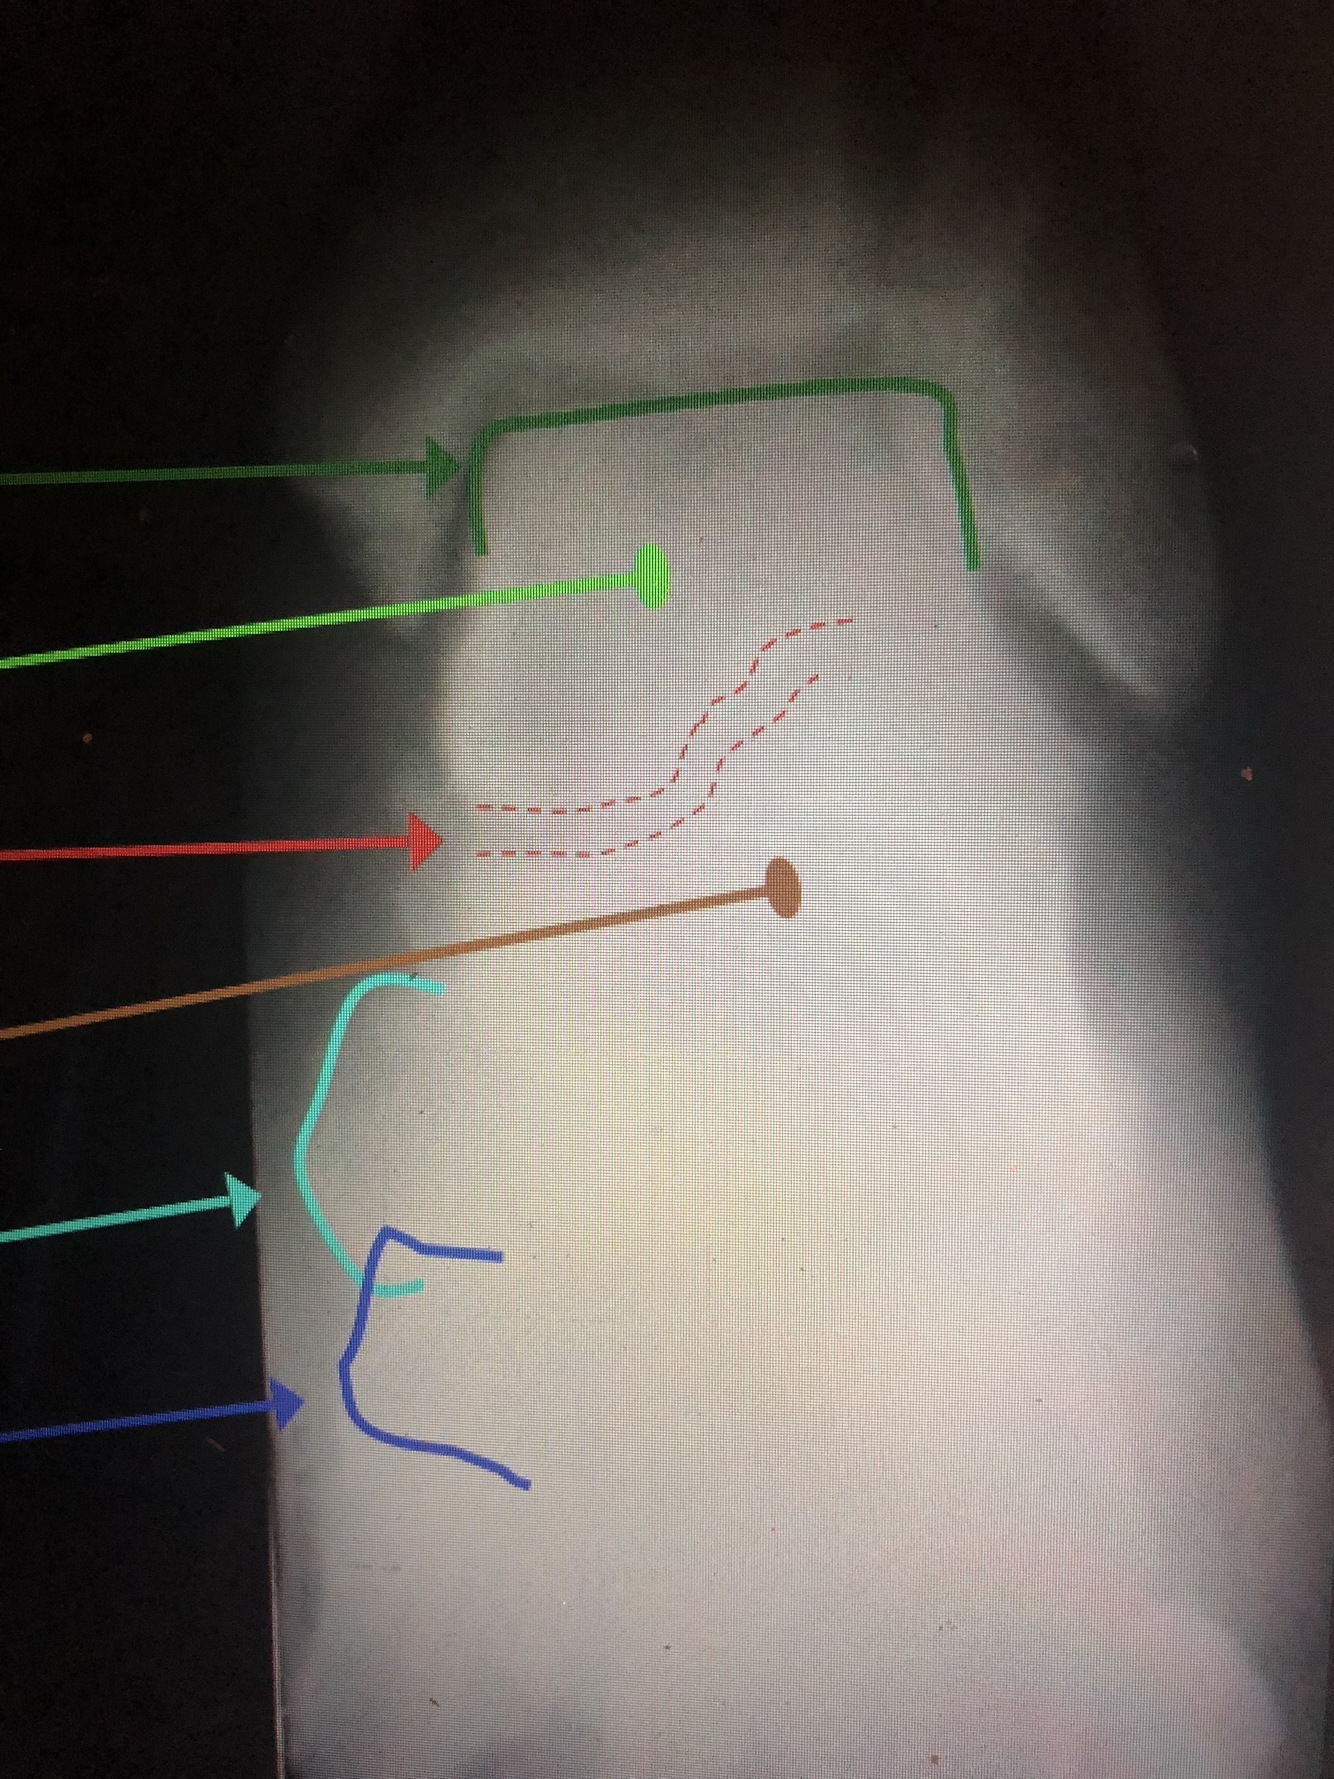

What is the green?

distal Fibular Shaft

What is the red?

Lateral Malleolus

What is the light blue dotted line?

Malleolar Fossa

What is the dark green line?

Talar Dome (Trochlea)

Which bone is the light green?

Talus

What is between the red dotted lines?

Talocalcaneal (Subtalar) Joint

What bone is the brown?

Calcaneus